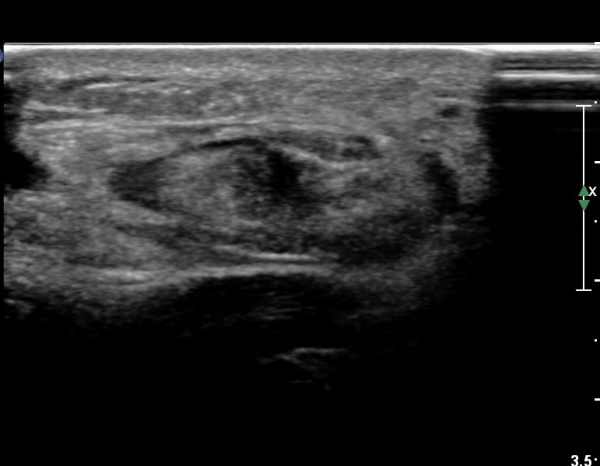

¾ÆÅ³·¹½º°Ç Á¾´Ü¸é°Ë»ç¿¡¼ ¾ÆÅ³·¹½º°Ç Àú¿¡ÄÚ ºÎÁ¾, ¿¬°á¼º ¼Ò½Ç, °ÇÁÖÀ§ ¼ö¾×Àú·ù ¼Ò°ßÀ» º¸ÀÓ(»çÁø 2, 3, 4, 5).